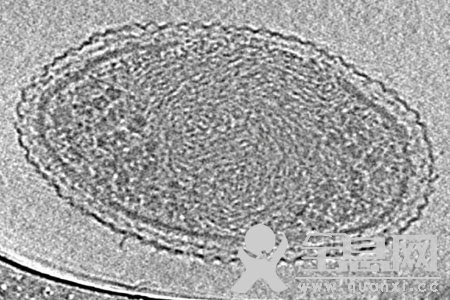

传统观点认为,在人们死前一刻,心脏扮演着重要角色。该观点认为心脏停止跳动之后,血液也开始停止流动,身体剩下的部位也开始停止运作。但新研究认为这种观点可能有误。科学家研究了缺氧而亡的小鼠,在死之前其心脏和大脑的活动。研究发现小白鼠的大脑在它死之前会给心脏发送一连串信号,给心脏造成了不可撤销的损害,并导致了它的最终死亡。研究人员将这一信号锁定之后,心脏存活的时间更久。